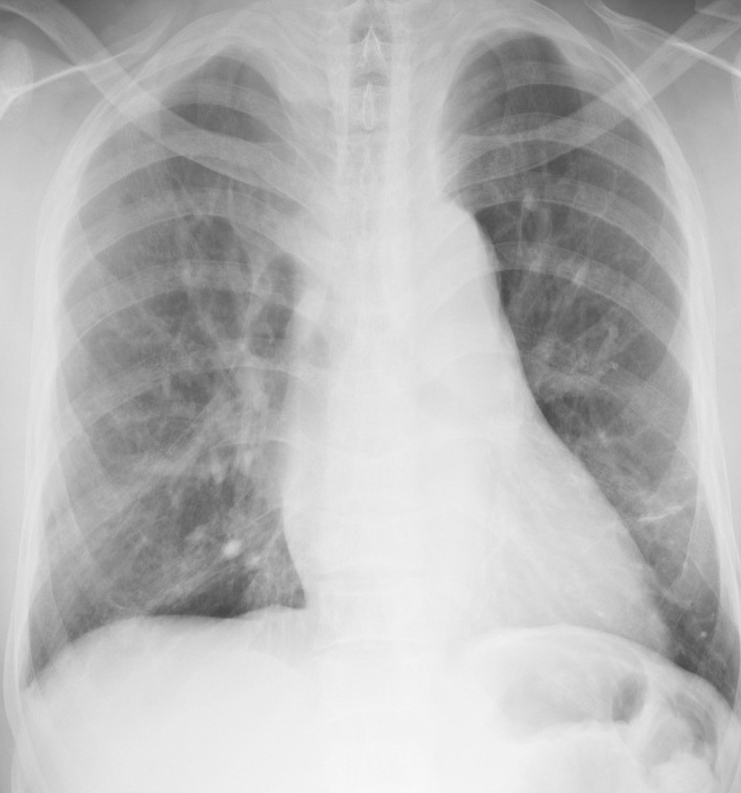

Figure 6 presents image examples for each class retrieved from the RYDLS-20 database. It is worth to mentioning that we have no further information concerning the CXR images with regarding the CXR machine used to take the image, as well as the origin, age and ethnicity of the people whose these images belong to.

Refer to caption

(c) SARS.

Figure 6: RYDLS-20 image samples.